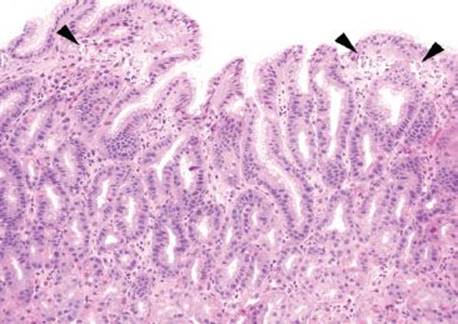

Gastric iron deposition is seen in up to 3.8% of upper tract biopsies (Fig. 2.228).23,24,183–185 In a study of 500 gastric biopsies, the deposition was demonstrated in three generalized patterns. Pattern A (also referred to as “nonspecific gastric siderosis”) was the most common subpattern and involved 2.2% of specimens (Figs. 2.229 and 2.230). This subpattern was associated with prior mucosal microhemorrhages, and the subtle depositions were predominantly identified within macrophages and stromal cells of the lamina propria. Pattern B (also referred to as “iron pill gastritis”) was seen in 0.8% of the biopsies and was consistently associated with ferrous sulfate therapy. This deposition was coarse and crystalline and predominantly identified in the extracellular and most superficial aspect of the biopsy (Figs. 2.231–2.234). In this subpattern, the background mucosa had a reactive gastritis/gastropathy pattern with erosions, ulcerations, and fibrino-inflammatory exudate common. In a separate study of 1,300 gastric biopsies, a similar “iron pill gastritis” injury pattern was detailed.184 This latter group reproduced the identical iron deposits in the laboratory by oxidizing ferrous sulfate tablets, providing clear evidence for the iron origin of these deposits. The mechanism of injury is a bit unclear in this subpattern. Some speculate that the iron pill has a direct caustic effect on the adjacent mucosa, whereas others suggest that the iron deposits may simply colonize previously injured mucosa. Pattern C (also referred to as “gastric glandular siderosis”) was the least common pattern, involving 0.6% of the specimens. This subpattern was associated with iron overload settings, such as hereditary hemochromatosis and multiple blood transfusions. The characteristic deposits were subtle, uniform, and identified in the deep antral and oxyntic glands (Figs. 2.235–2.239). The iron deposits can be highlighted blue with a Prussian blue iron special stain. Recognition is important to help prevent further injury and potential stricture formation (pattern B), to suggest pertinent iron overload evaluation (pattern C), and to avoid overdiagnosing the marked reactive epithelial change as dysplasia.

Figure 2.235 Iron pattern C/“gastric glandular siderosis”. This iron pattern can be one of the more difficult to recognize because of the subtle and uniform findings that are not very apparent at low power (bracket). Nonetheless, it can be critical to appreciate since it indicates iron overload and may prompt genetic testing for hereditary hemochromatosis, in the appropriate clinical setting. The more common setting, however, is a transfusion dependent patient, as in this case. This patient had a history of lymphoma, bone marrow transplant, and was known to have iron overload syndrome based on the history of extensive blood transfusions.